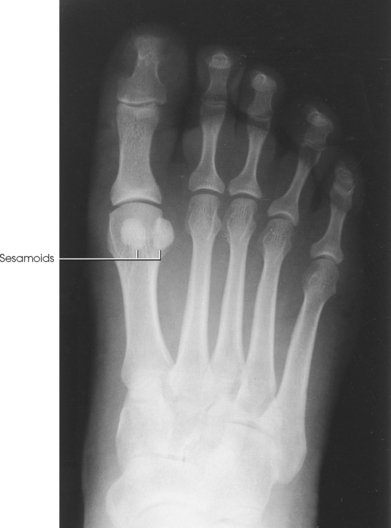

Beneath the head of the first metatarsal are two small bones called sesamoid bones. They are detached from the foot and embedded within two tendons. These bones are seen on most adult foot radiographs. They are a common site of fractures and must be shown radiographically (see Fig. 6-2).

Structures shown: The resulting image shows a tangential projection of the metatarsal head in profile and the sesamoids (Fig. 6-35).